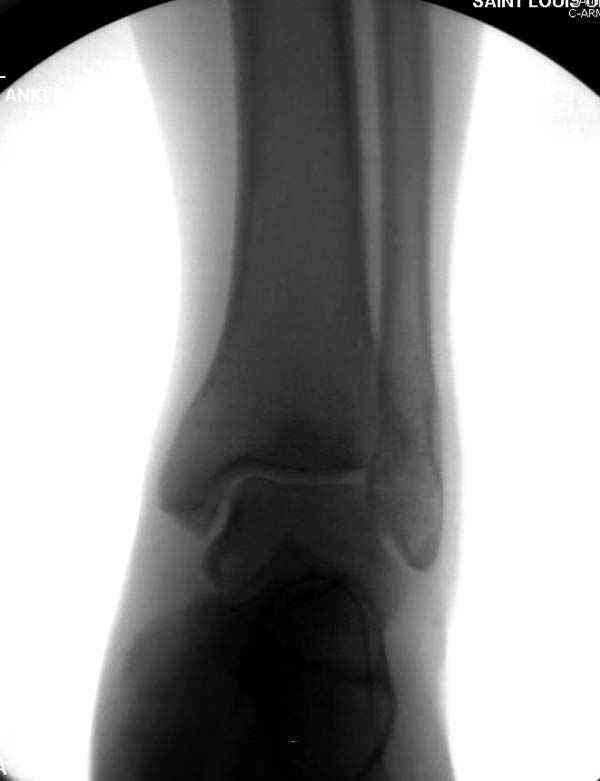

Нет первичных снимков, перелом очень низкий и под большим сомнением диагноз разрыва синдесмоза. Медиальная сторона отрепонирована на "хорошо" и, по-видимому, прорезание проволоки произошло во время операции. Без снимков трудно судить о высоте малоберцовой, а лодыжка находится в варусе. Лагирование получилось, но возле тонких шурупов передне-задний шуруп выглядит немного тяжеловато.

Здесь несколько частных случаев: перелом голеностопа со сравнительными снимками и разрыв синдесмоза, а также медиальная Hook пластина.